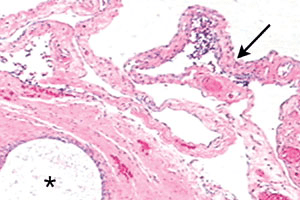

Figure 8 : Ces glandes individualisées d’une endométriose superficielle du ligament large gauche n’ont pas été détruites par la vaporisation laser, alors que des adhérences fines et transparentes sont une conséquence du traitement au laser (pour l’aspect microscopique, voir la figure 9).

Figure 9 : Une glande d’endométriose (astérisque) se trouve juste au-dessous du péritoine de la patiente (figure 8). Des adhérences transparentes (flèche) peuvent se développer suite à un dégât de la chirurgie au laser.